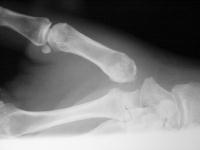

Another xray before surgery

and after surgery.